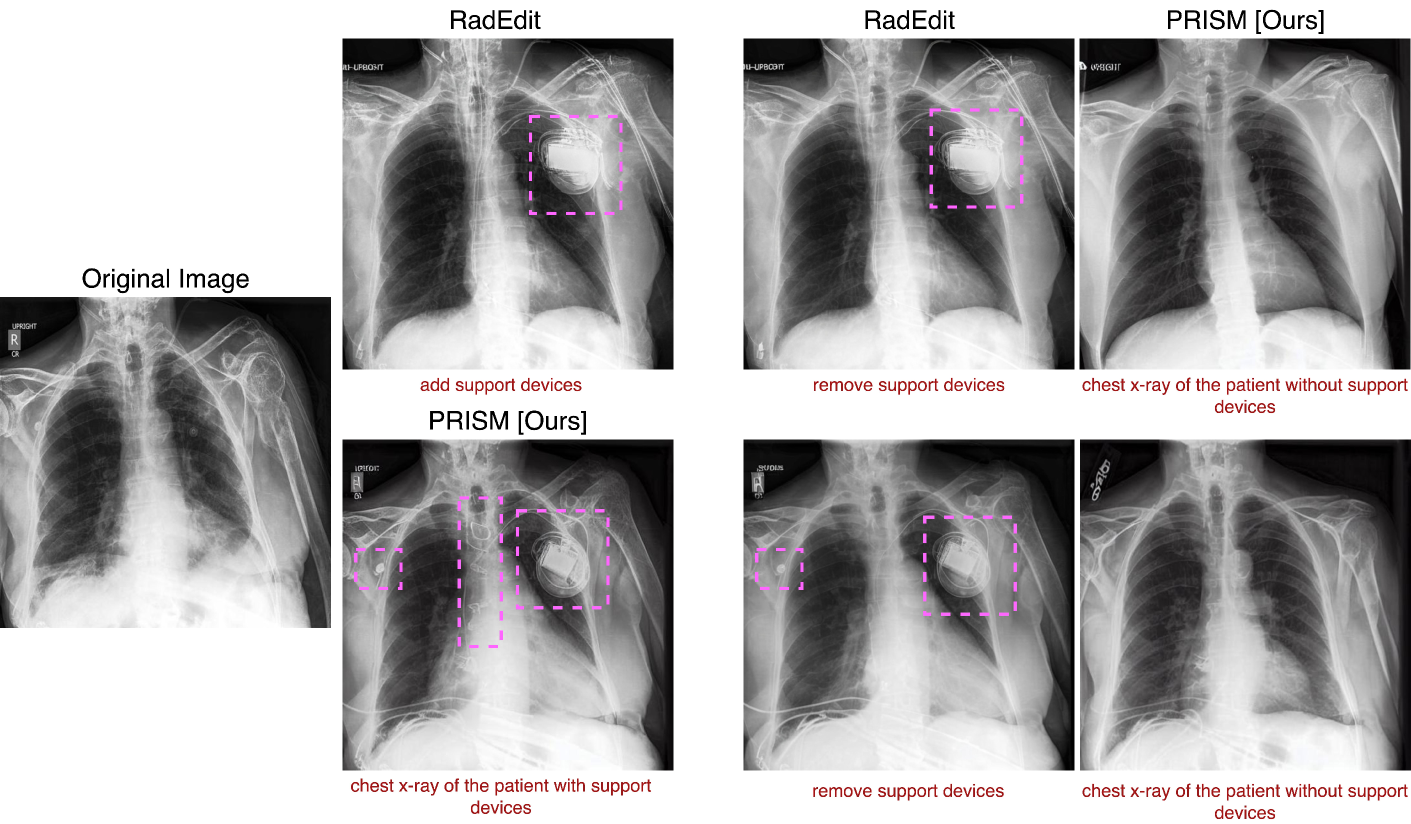

Fig. 6 show PRISM performs significantly better than RadEdit, Imagic, and Null-text inversions for removing devices from the original image. It should be noted that the methods Imagic and Null-text inversion were originally deployed with Stable Diffusion 1.4. For a fair comparison to PRISM, these two architecture use the same fine-tuned model as the PRISM for synthesizing images in Fig. 6.

B.1 Sequential Image Editing

The image-editing performance of PRISM was evaluated against RadEdit [Pérez-García et al.(2025)Pérez-García, Bond-Taylor, Sanchez, van Breugel, Castro, Sharma, Salvatelli, Wetscherek, Richardson, Lungren, et al.] in sequential image-editing scenarios. Fig.  7 presents a comparative demonstration where both methods were tasked with first adding and then removing a medical support device from an image. While RadEdit successfully added medical devices to the image, it shows limitations when attempting to remove these same devices.

Refer to caption

Figure 7: Sequential editing comparison: RadEdit (top) and PRISM (bottom) first add a support device to the original image. When prompted to remove these support devices, RadEdit fails or only partially succeeds, while PRISM successfully removes them completely. Note that RadEdit operated without masks in all experiments.